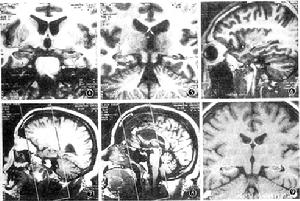

2.MRI解剖(T1加權像):海馬結構信號與皮層相同,體、尾部境界清楚,在頭部,可藉助表面高信號的海馬槽及側腦室顳角尖與杏仁核分開,但與海馬回鉤之間需據解剖劃分(圖4~6)。儘管Miller等[3]報導使用3.0T MR 機能識別海馬細節,但目前大部分MR機無法分辨。

1.磁共振成像:採用Siemens 1.0T超導MR系統。52例作自旋迴波(SE)序列,垂直於海馬長軸的傾斜冠狀位T1加權像:TR、TE分別為540、15毫秒,採集次數2次,視野230mm,矩陣190×256 ,層厚4mm,無間距,採集時間4分1秒,16幅圖像。我們結合臨床把掃描野的後界定在後連合,前緣包括顳極(圖7,8)。25例還做三維磁化準備快速梯度回波(three dimensional magnetization prepared rapid gradient echo,3D MPRAGE)序列成像,TR、TE分別為14、6毫秒,反轉時間(TI)400毫秒,激勵角11°,視野250mm,矩陣190×256,採集時間6分17秒,32幅圖像。位置、層厚和層距與SE序列一致,掃描平面兩側對稱。SE序列海馬結構掃描範圍僅包括了頭部、體部及部分尾部,而3D MPRAGE序列包括整個海馬結構。

2.體積測量:海馬結構體積測定方法與Jack等[4]相同:調節合適的窗位、窗寬,明確海馬邊緣,在每一個平面用滑鼠勾畫出海馬結構的邊緣,獲得其面積,根據層厚計算出體積,在海馬頭部要根據解剖與鉤、杏仁核區分(圖9)。